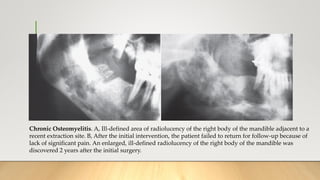

Chronic Osteomyelitis. A, Ill-defined area of radiolucency of the right body of the mandible adjacent to a

recent extraction site. B, After the initial intervention, the patient failed to return for follow-up because of

lack of significant pain. An enlarged, ill-defined radiolucency of the right body of the mandible was

discovered 2 years after the initial surgery.